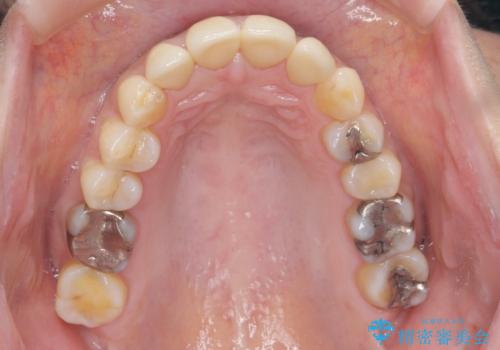

前歯をきれいな被せ物にしたい。

- 前歯の形が気に入らなく、粗造な感じがして色も気に入らないとの事で来院。

ホワイトニングは以前行っていてもうやりたくないとの事でした。

虫歯になっている歯はないので、患者様としっかり相談をして被せ物治療をする事に致しました。

適合の良い被せ物が入りました。

樹脂の素材とは違い、セラミックやジルコニアの素材の被せ物は劣化をしません。また、虫歯の再発リスクも低くなります。

形、色、共に満足して頂けました。